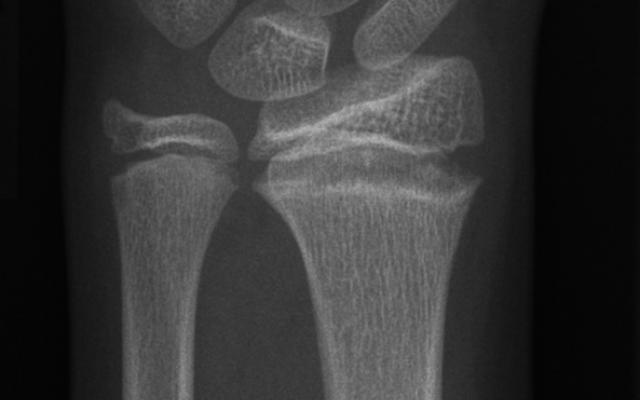

Een 11-jarige turnster kwam op de polikliniek Sportgeneeskunde met pijn aan beide polsen die sinds 1 jaar bestond. Patiënte vertelde dat de pijn tijdens en na elke training optrad. Anamnestisch was er geen evident trauma bekend. Bij lichamelijk onderzoek zagen wij een niet-afwijkende stand van de polsen, zonder zwellingen of bewegingsbeperkingen. Als de polsen in de eindstanden van dorsale en palmaire flexie werden bewogen, was dit rondom de gehele pols gevoelig. Alle weerstandstesten waren positief, maar de kracht was niet verminderd. Een röntgenfoto van de linker pols toonde een verwijding van de epifysairschijven en onregelmatige contouren van de metafysen…